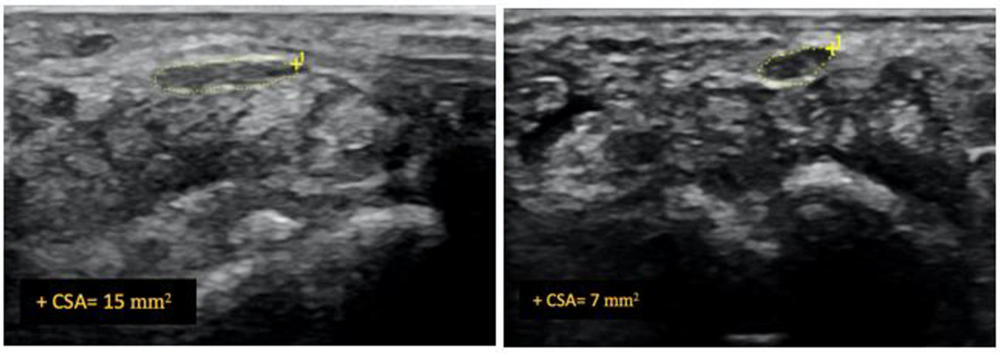

Additionally, ultrasounds showed a significant reduction of median nerve cross-sectional area in both hydrodissection groups. Group one showed a reduction of 43%, and group two showed 46%. Group three showed only an 11% reduction.

Figure 2. Ultrasound image of median nerve before and after hydrodissection procedure in a patient with carpal tunnel syndrome. This case had cross-sectional area of 12 mm2 pre-procedure that reduced to 7 mm2 post-procedure (dashed yellow lines depicting the median nerve).

High-res (TIF) version